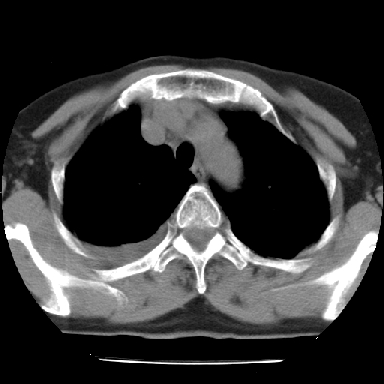

以下是引用苯小孩在2007-4-13 16:20:00的发言:[br]1、右下肺中央型肺癌并阻塞性肺不张、肺内转移、胸椎右侧附件亦有转移<横断层面第8层>.[br]2、右侧胸腔积液.

以下是引用swyyy2007在2007-4-13 15:31:00的发言:[br]右肺门下区肿块,右肺下叶支气管阻塞,右肺下叶不张,右侧大量胸腔积液,右肺中叶见结节状高密度影,边缘清,纵隔内见肿大淋巴结。首先考虑右下肺中心型肺癌伴右肺下叶不张、中叶、纵隔淋巴结转移。右侧胸腔积液。